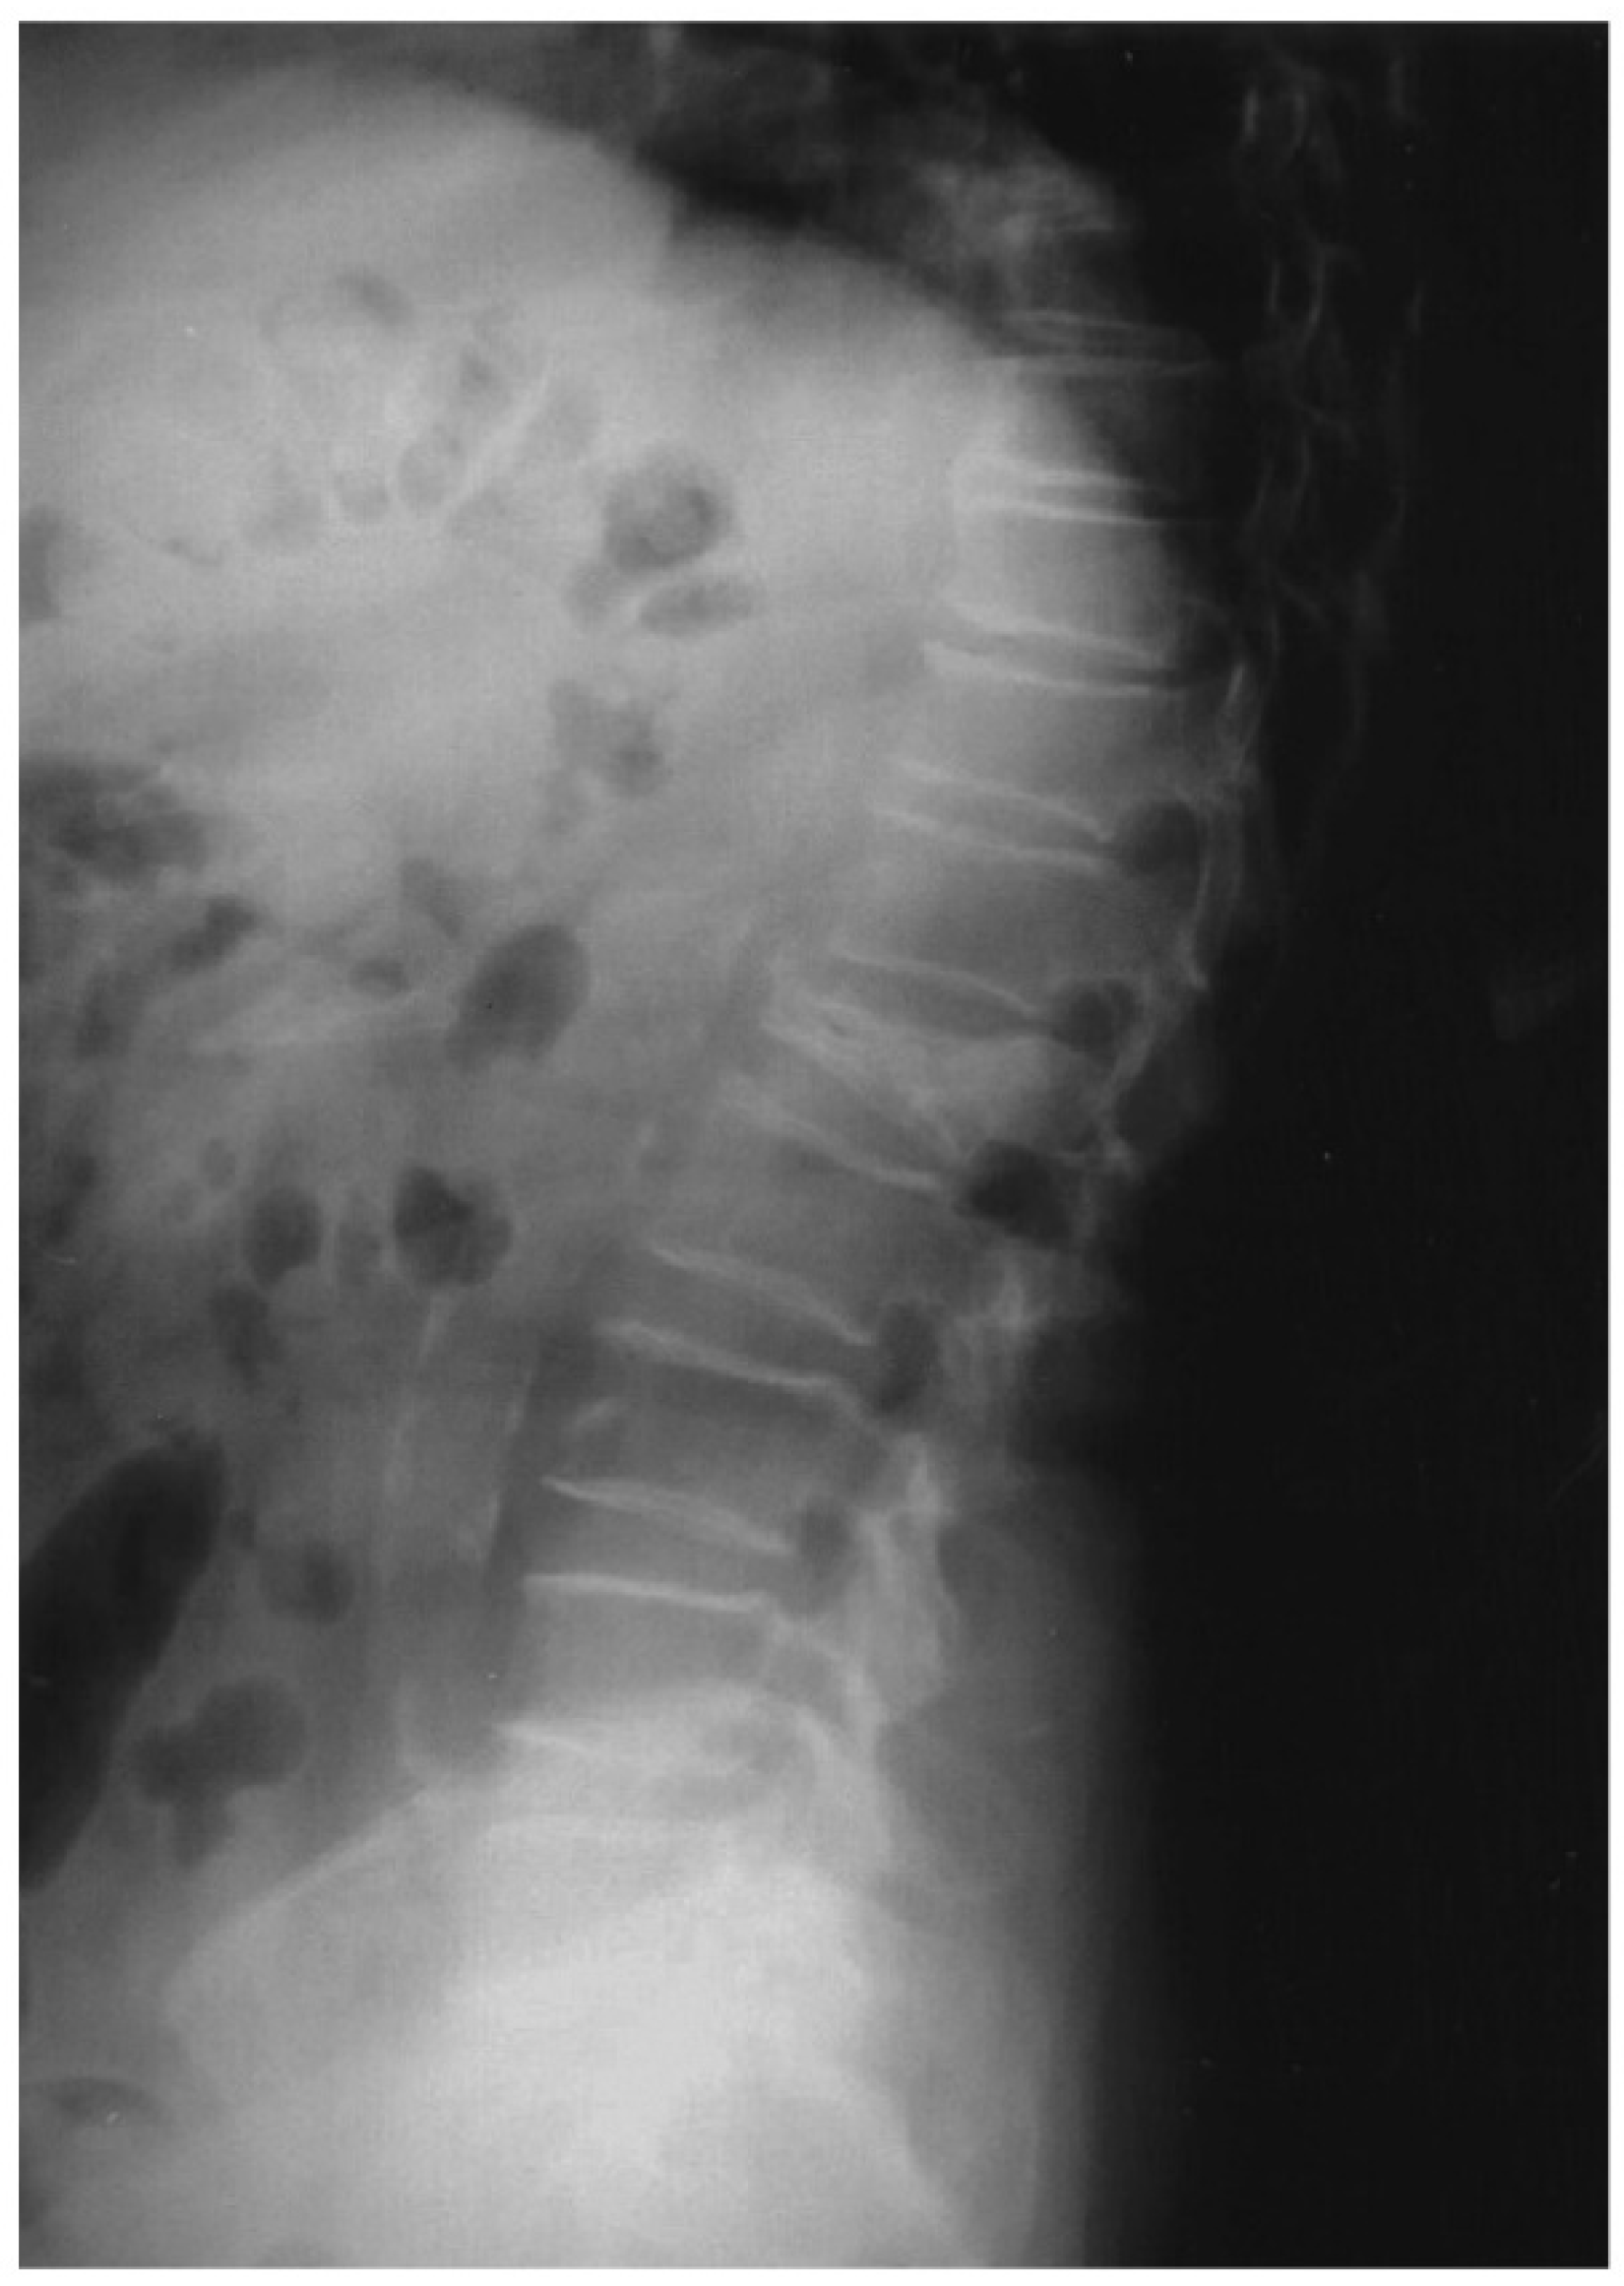

- Naves, M.; García, M.R.; López, J.B.D.; Alonso, C.G.; Andía, J.B.C. Progression of vascular calcifications is associated with greater bone loss and increased bone fractures. Osteoporos. Int. 2008, 19, 1161–1166. [Google Scholar] [CrossRef]

- Fusaro, M.; Tripepi, G.; Noale, M.; Vajente, N.; Plebani, M.; Zaninotto, M.; Guglielmi, G.; Miotto, D.; Carbonare, L.D.; D’Angelo, A.; et al. High Prevalence of Vertebral Fractures Assessed by Quantitative Morphometry in Hemodialysis Patients, Strongly Associated with Vascular Calcifications. Calcif. Tissue Int. 2013, 93, 39–47. [Google Scholar] [CrossRef]

- Rodríguez-García, M.; Gómez-Alonso, C.; Naves-Díaz, M.; Diaz-Lopez, J.B.; Diaz-Corte, C.; Cannata-Andía, J.B.; the Asturias Study Group. Vascular calcifications, vertebral fractures and mortality in haemodialysis patients. Nephrol. Dial. Transplant. 2008, 24, 239–246. [Google Scholar] [CrossRef] [Green Version]